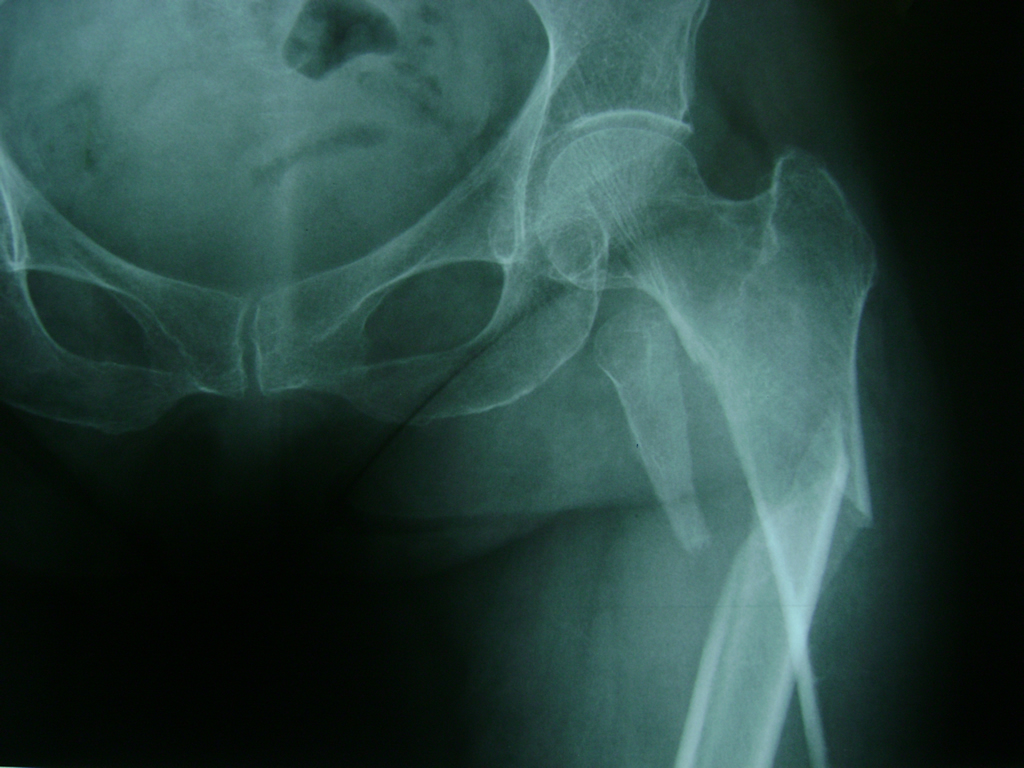

La cirugía de fractura de cadera se realiza para reparar una ruptura en la parte superior del hueso del muslo. Este hueso se denomina fémur.

Es parte de la articulación coxofemoral. Si una fractura de cadera no recibe tratamiento, es posible que deba permanecer en una silla o en la cama.